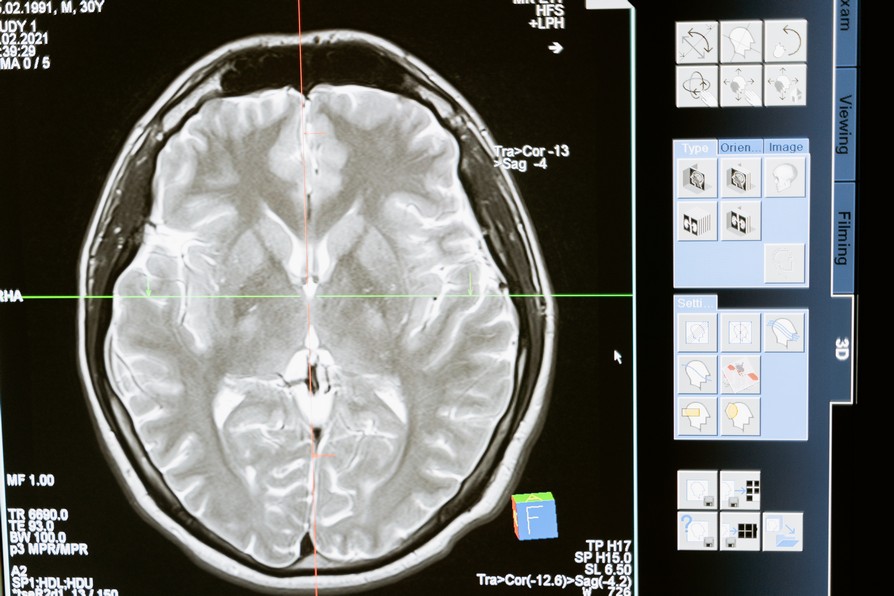

After a concussion, a medical imaging test can be performed. Mostly, this is a CT-scan of the brain.

CT scans and concussion diagnosis

CT-scans can reveal brain damage, but this is not always the case for mild TBI. In fact, about 90% of the CT-scans after experiencing mTBI do not show abnormalities.

So, CT abnormalities can prove that there is something off in the brain. But a positive CT diagnosis is not a necessity for explaining your symptoms after sustaining a concussion. You might find it reassuring to know that this has also been confirmed in research recently.